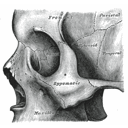

facial bones.jpg

lacrimal bones.jpg

mandible.jpg

maxillary bones.jpg

nasal bones.jpg

palatine bones.jpg

zygomatic bone.png